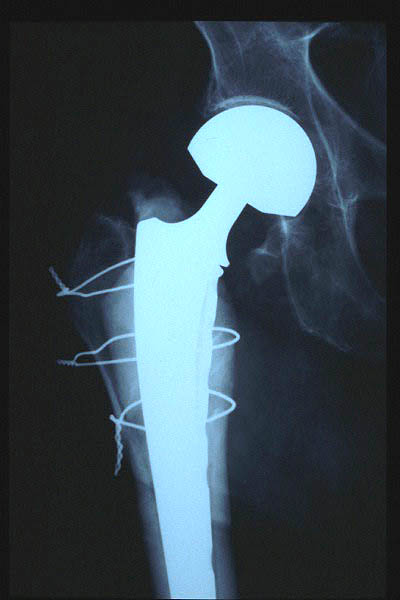

Fractura cuello fémur. Prótesis completa.

Fractura intertrocantérea de fémur, osteosíntesis

Fractura de fémur, prótesis parcial de cadera

osteosíntesis fractura fémur

Prótesis parcial de cadera

Prótesis de cadera.